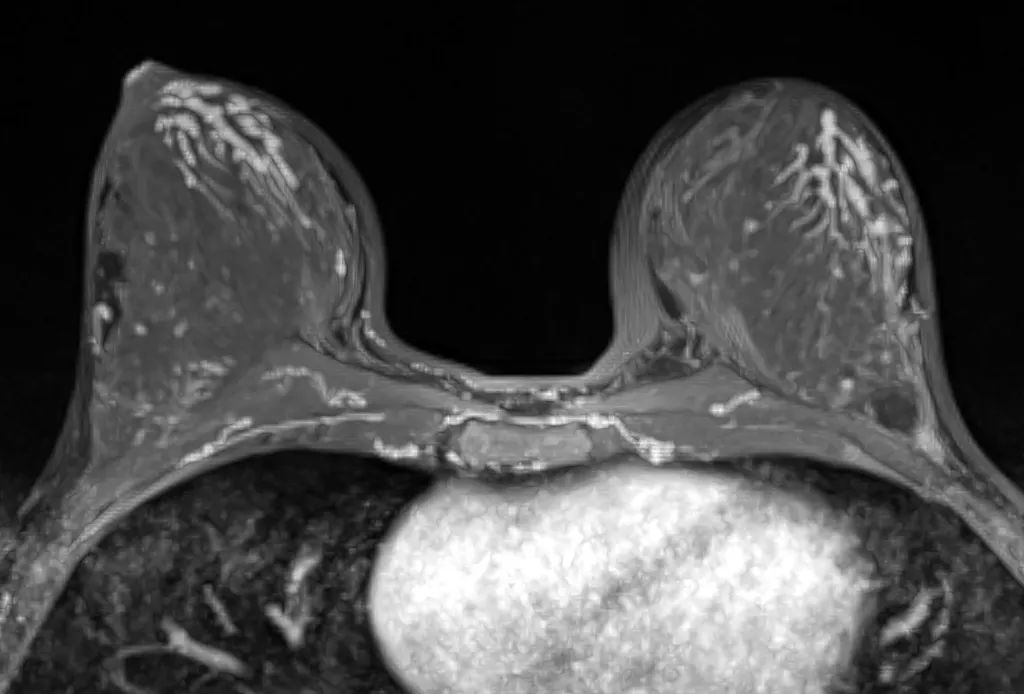

先説説這個乳腺結節,

乳腺結節在女性中很常見。

乳腺結節並不是一種病,

它是指乳腺形態的改變。

乳腺結節主要分兩類,

一類是由乳腺增生引起的,

一類是由良性或者惡性的腫瘤引起的。

不過先不要慌,

因為乳腺結節80%以上都是良性的,

惡性情況比例還是比較低的。